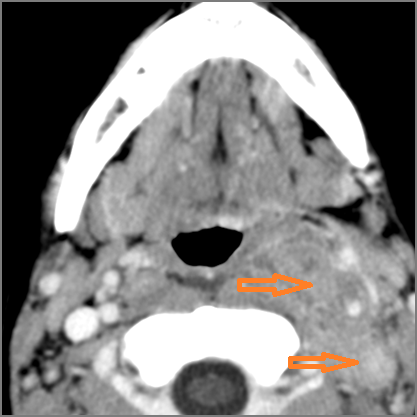

26-year old male in the emergency room with fever, sore throat and neck swelling.Exam

Severe suppurative pharyngitis and advanced suppurative lymph adenitis with no evidence of abscess.